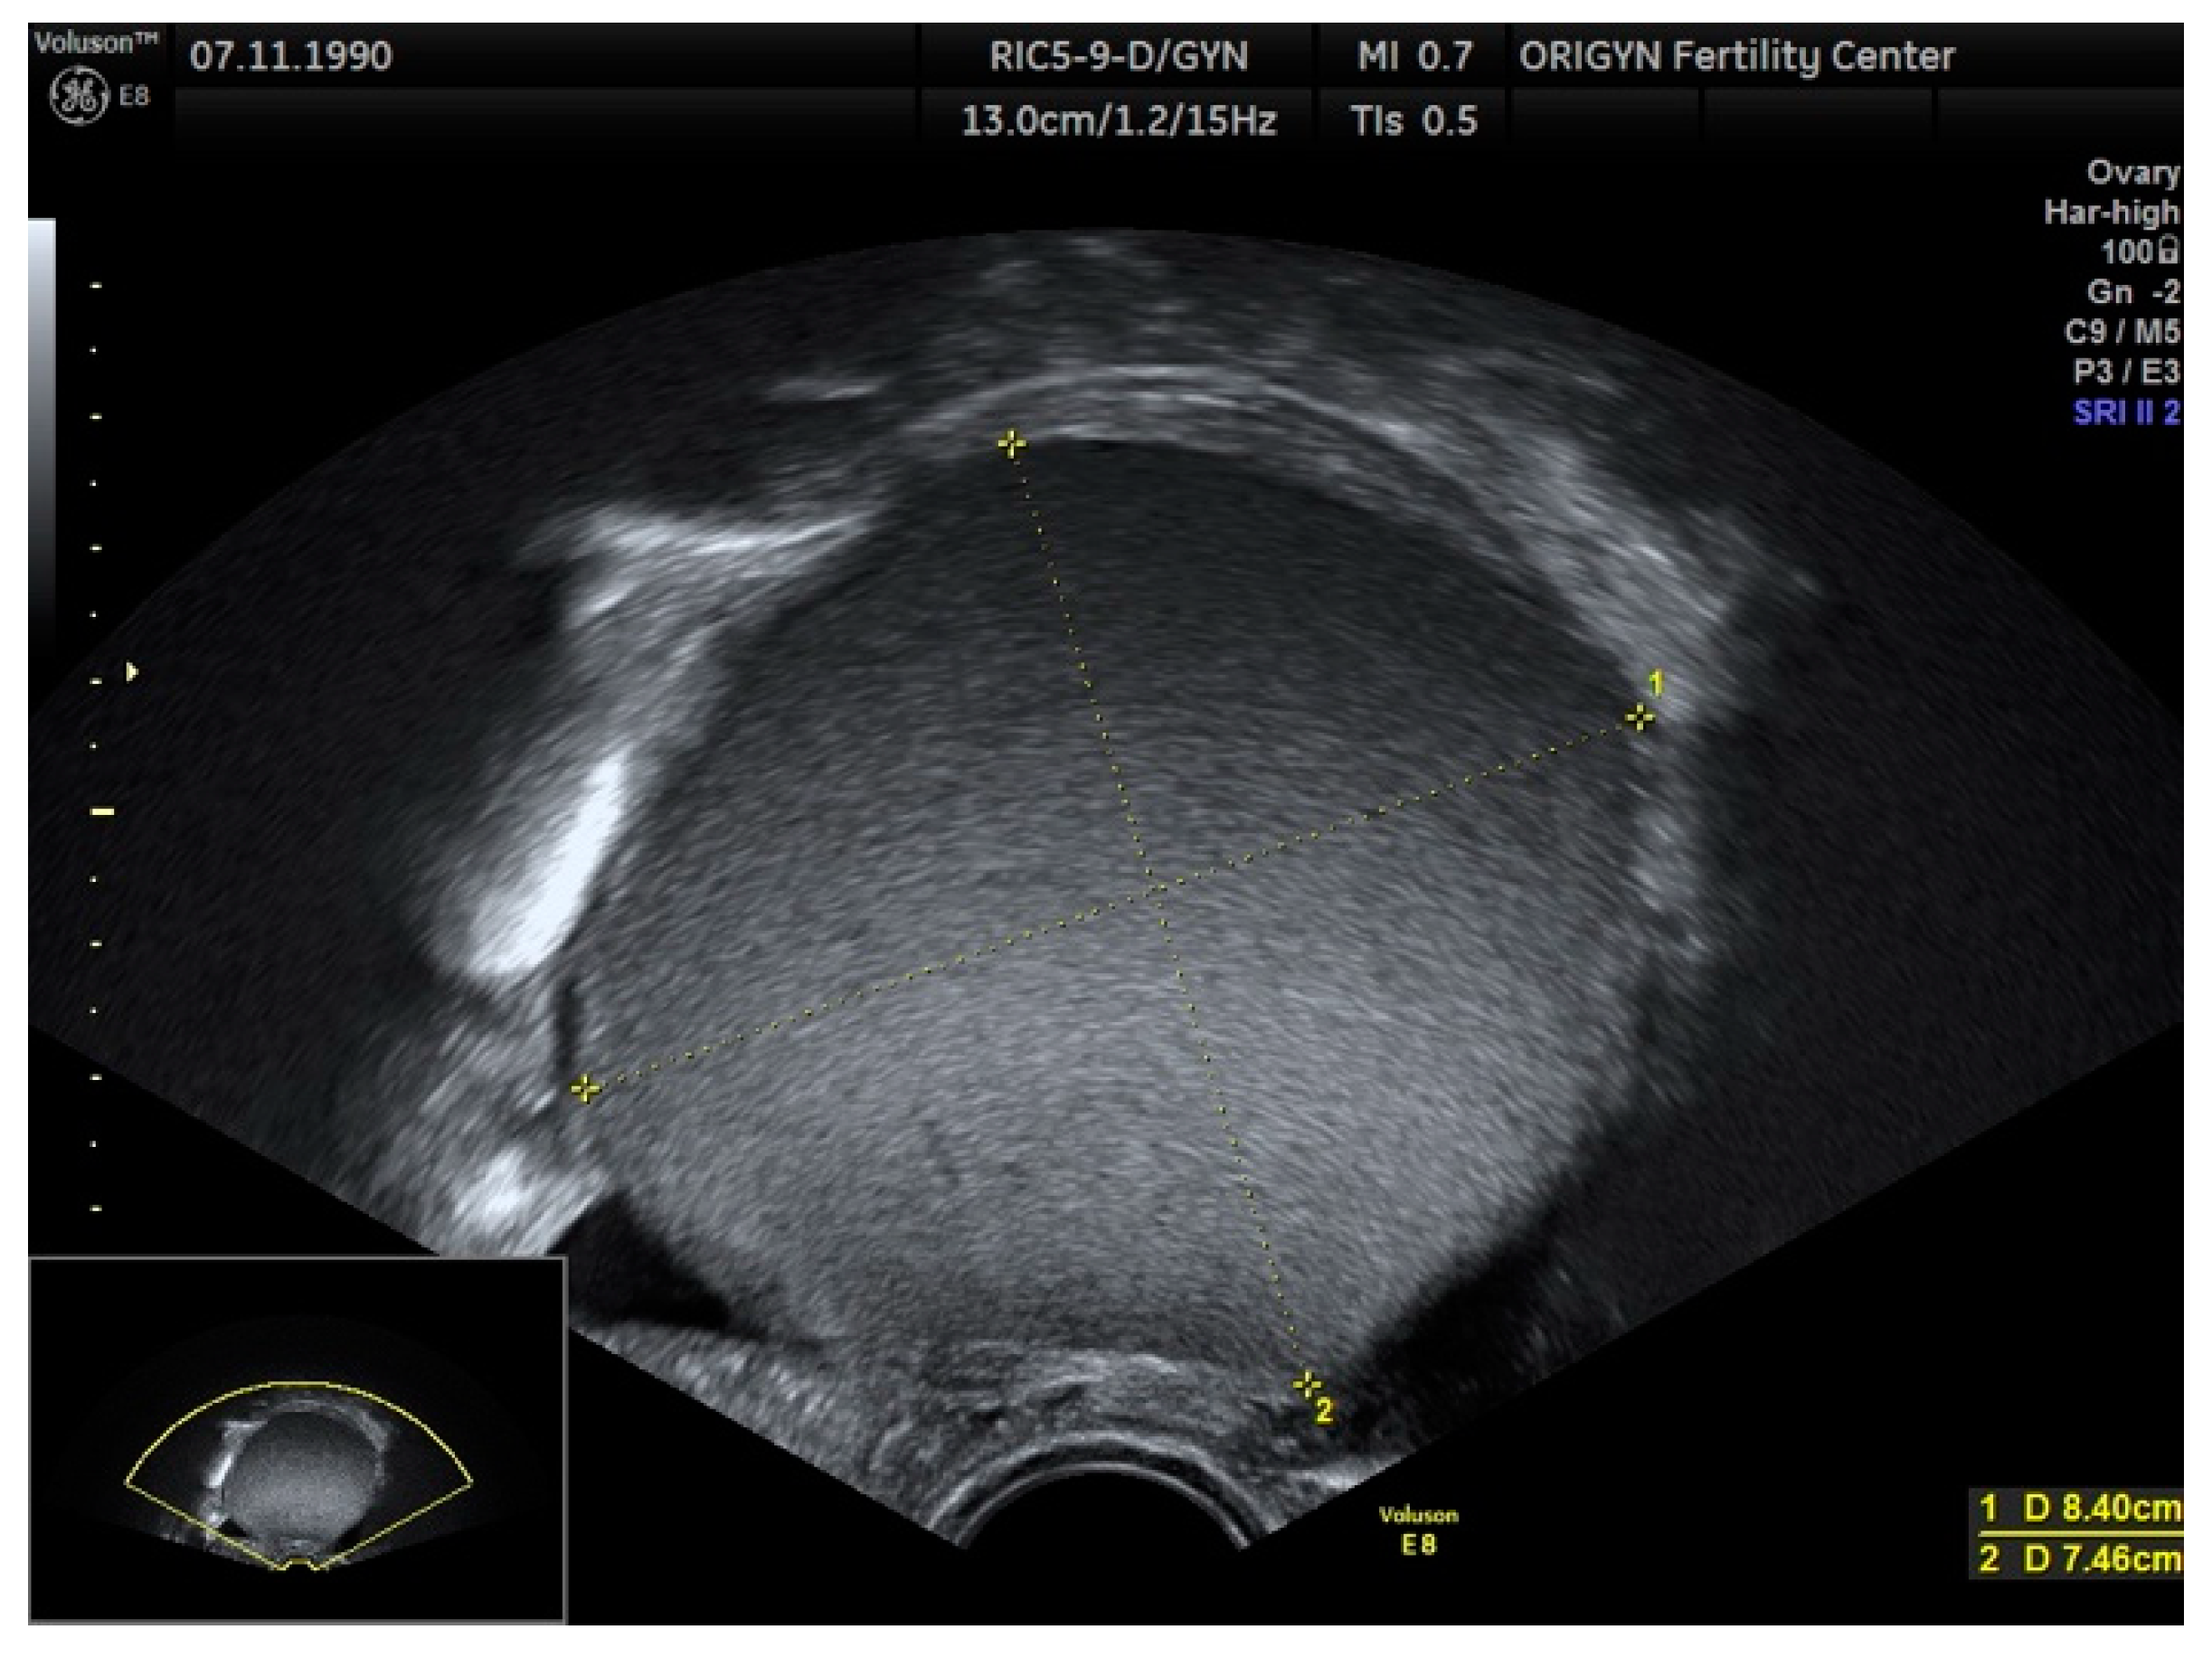

3.1. ADNEXA